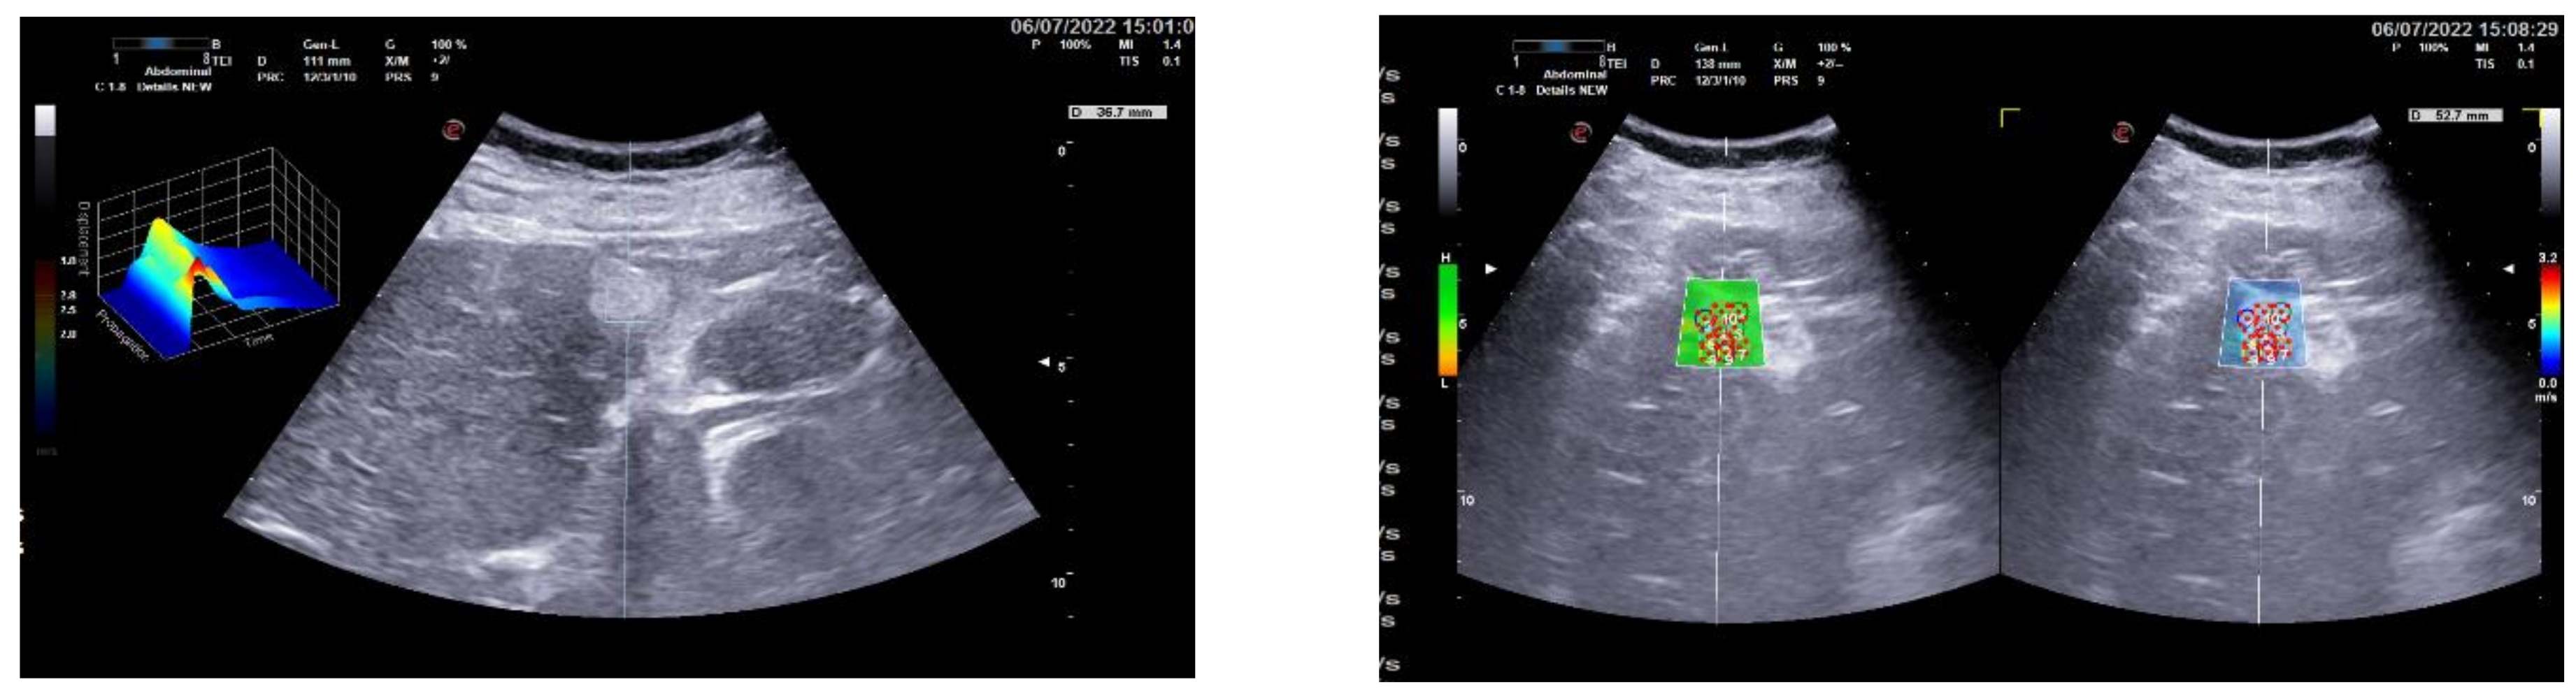

3.2. Group 2: Malignant Focal Liver Lesions (Hepatocellular Carcinoma)